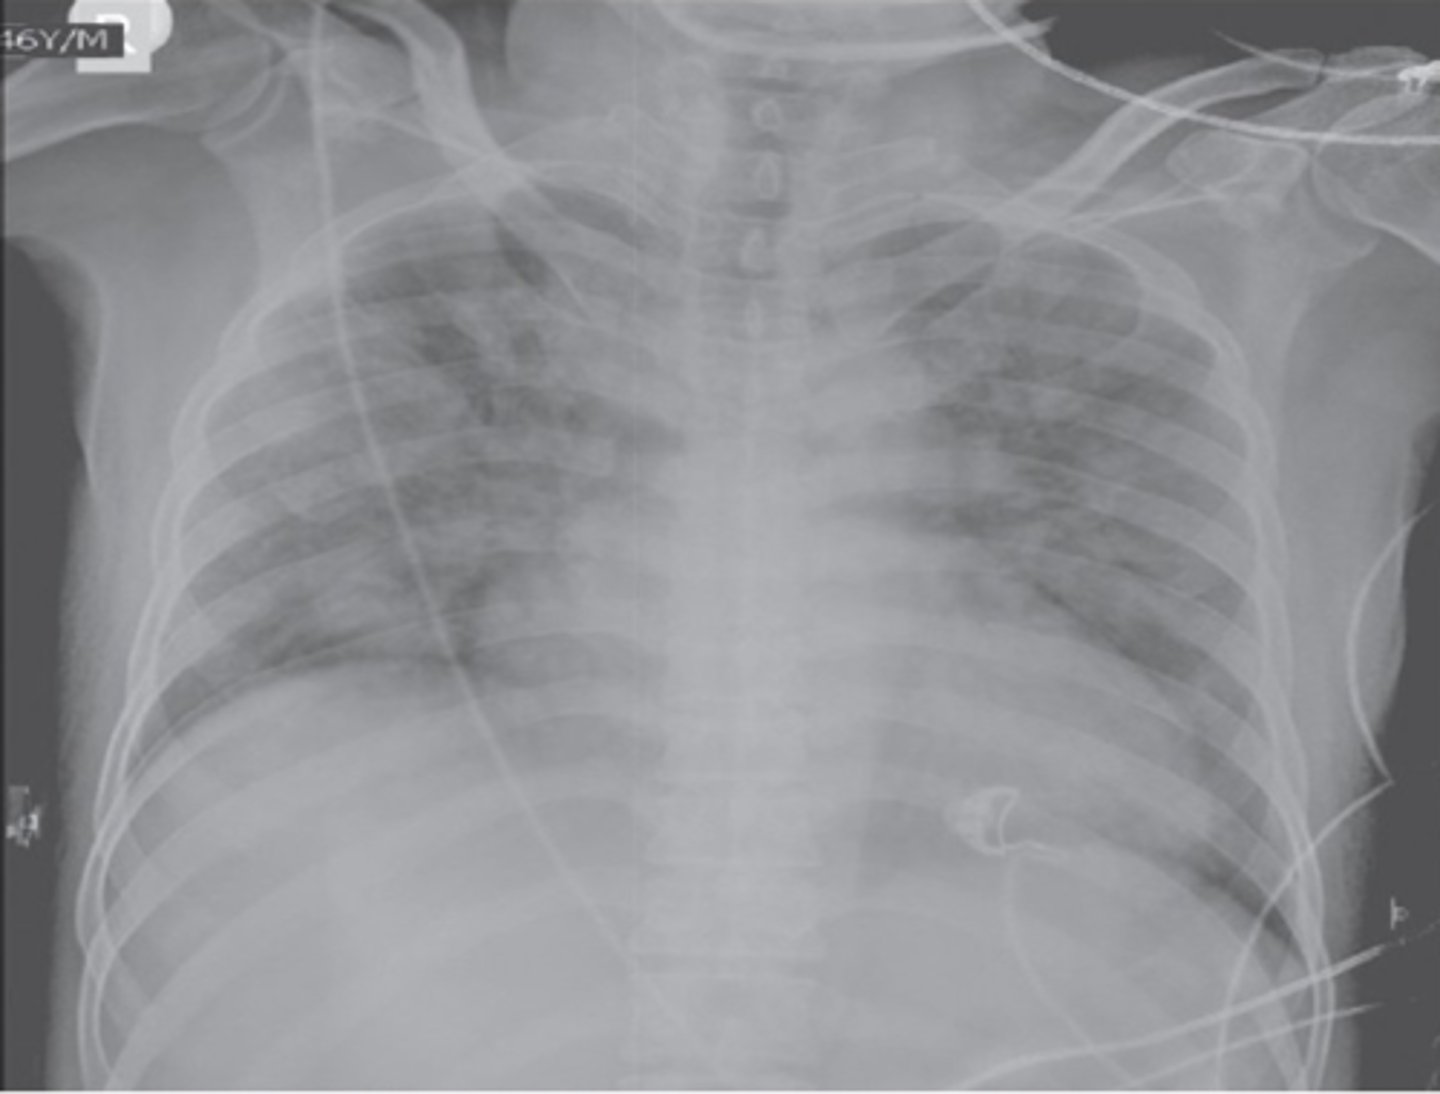

tachycardia, cough, dyspnea, hypertension; cardiomegaly and pulmonary edema are seen on CXR

What are signs and sx of Transfusion-Associated Circulatory Overload (TACO)?

measuring a BNP/NT-proBNP may assist; echocardiogram (know your patient’s EF)

How is Transfusion-Associated Circulatory Overload (TACO) dx?

diuresis and supplemental oxygen; ventilation support may be required

Non-cardiogenic pulmonary edema causing acute hypoxemia within 6 hours of the transfusion with clear temporal relationship to the transfusion

What is Transfusion-Related Acute Lung Injury (TRALI)?